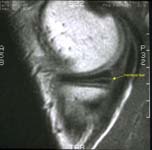

An MRI can be used to confirm the diagnosis of a torn meniscus. See Figure 5.